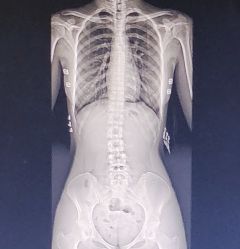

popo,肥刚确诊了脊柱侧弯,医生说成年了没法矫正了( ;´д`)

>>No.63406962

如果有需要的话,可以去正经中医院的正骨推拿科,理论上可以慢慢矫形,但需要很长时间,另外最后结果也不会如原先的骨骼一样,通常会建议不影响正常生活的话暂时不管它(`・ω・)

这个要看肥哥怎么定夺(`・ω・)

无标题 无名氏 2024-08-10(六)18:48:55 ID:zuGC8ld [举报] No.63409057 管理

我看的医生也是这么说的。中医馆的医生说我盆骨也有点问题,最近久坐左腰会不舒服,但是帮我正骨了感觉没什么效果(;´Д`)

>>No.63409057

平常翘二郎腿吗(`・ω・)

这个片子看起来是像右凸向左弯(应该是,当然不同医院片子方向可能不一样),骨盆感觉有点不对称,腰1开始歪的,可以练点功能锻鍊,具体是右边(脊柱凸的那边)侧躺在床上,把枕头或被子垫在弯的那一段下面,每天躺一段时间,配合吊单杠(纯吊住)和靠墙举手站立可以一定程度的恢复

另外片子看起来是卿卿,如果骨盆不对称的话怀孕及产后都容易有腰背及下肢的症状,产后也更容易出现咳嗽大笑大幅度跨腿等动作时漏尿,建议及早治疗以免影响生活质量

最后,不建议赛博求医,但可以跟医生说在胸12腰1那边做连椅凳坐姿旋转复位,腰2往下在床上趴着摆腿复位,骨盆做斜扳法

(我不知道其他医院有连椅凳没有,这东西貌似是我们医院设计让木工弄出来有专利的。没有连椅凳的话普通两张凳子也行(`・ω・))

无标题 无名氏 2024-08-10(六)19:16:58 ID:oq5L8xo [举报] No.63409302 管理

>>No.63409268

推拿手法上的话,首先用趴着的体位,沿着竖脊肌等背部肌肉尤其下背部及臀上皮神经和臀中肌掌揉指拨肘按,然后侧躺上面腿屈下面腿伸直肘按或点按下背部肌肉、臀上皮神经和梨状肌

无标题 无名氏 2024-08-10(六)19:18:51 ID:oq5L8xo [举报] No.63409315 管理

对,脊柱向右凸向左弯(`・ω・)